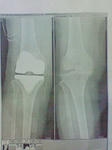

術後に、担当医師から説明があり

きれいに人工関節が入ったようです。

その時に渡された、レントゲンのコピーです。

右側のレントゲン写真を見ると、本当に骨がぶつかっていて

かなり、辛かったんだと思います。

母は、一緒に旅行に行った時から、歩くのが辛いって言ってましたけど